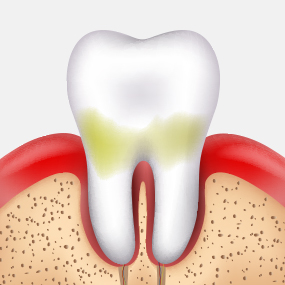

충치는 스스로 회복되지 않기 때문에,

정기적인 검진과 조기 치료가 건강한 치아를 오래 보존하는 가장 좋은 방법입니다.